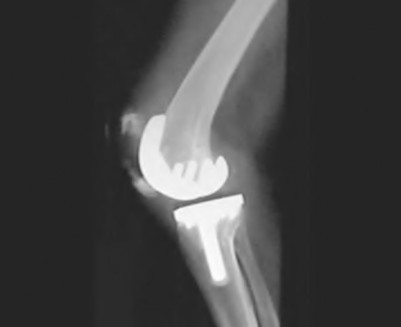

A 60-year-old male tennis player undergoes a unicompartmental knee arthroplasty (UKA) shown in Figures A and B. Which of the following statements regarding this procedure is true?

Figures A and B depict radiographs of a unicompartmental knee arthroplasty (UKA). UKA kinematics have been shown to most closely approximate native knee kinematics.

In an in vitro cadaver study, Patil et al found that TKA significantly changed knee kinematics while the unicompartmental replacement preserved normal knee kinematics.

Fisher et al performed a retrospective study comparing the short-term outcomes of small-incision unicompartmental knee arthroplasty (UKA) with standard total knee arthroplasty (TKA) in 91 consecutive patients older than 70 years. They found: 1) Blood loss was significantly more for the TKA group, as was the need for blood transfusion. 2) Patients with unicompartmental replacements had a much quicker return of function and discontinuation of pain medication. 3) While knee scores and ROM were similar preoperatively, both were better in the unicompartmental group at each postoperative time interval. 4) Narcotic use and length of hospital stay were also significantly less for the unicompartmental group. Therefore answers 2,3,4 and 5 are false.